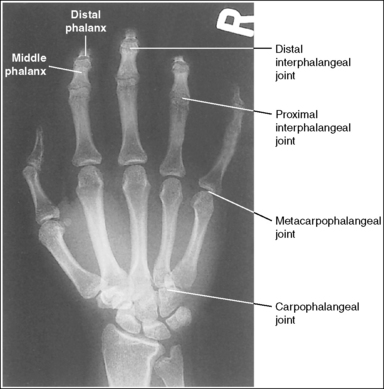

Hand: Posteroanterior Projection

See Figure 4-22 and Box 4-8.

The digits and metacarpals demonstrate a PA projection. The soft tissue outlines of the second through fifth phalanges are uniform, the distance between the metacarpal heads is equal, and the same midshaft concavity is demonstrated on both sides of the phalanges and metacarpals of the second through fifth digits.